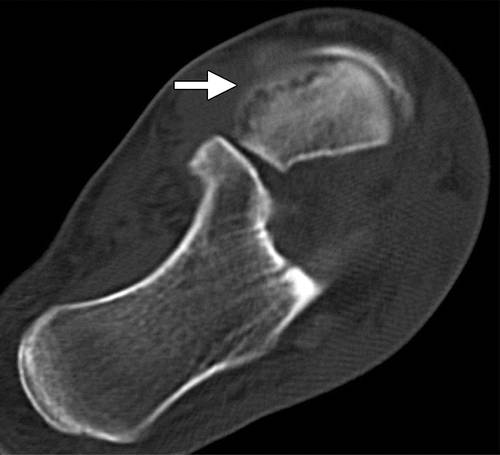

图13b后突骨折。 (a)右足的外侧X光片显示在距骨后方的小骨质碎片(箭头)。 (b)右脚的轴向CT图像显示后路过程骨折(箭头)以及粉碎的程度和程度。